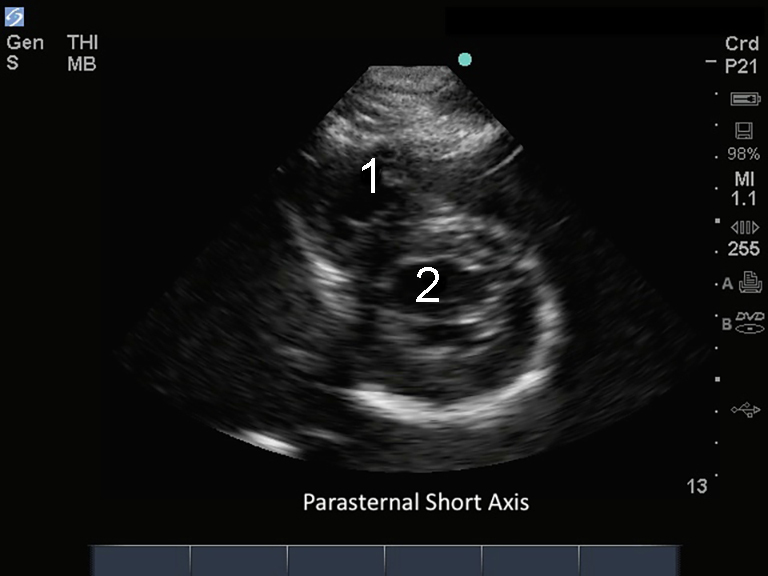

M-Turbo : Axe court parasternal

1. Ventricule droit (VD)

2. Ventricule gauche (VG)